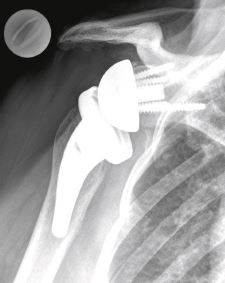

Im Bereich der Gelenkspfanne wird eine Metallkugel mit Schrauben fixiert. Auf der Gegenseite wird beim Oberarmkopf eine neue Pfanne aus Kunststoff und einem Metallschaft in den Oberarm fixiert. Die natürliche Biomechanik wird also «umgekehrt». Der kräftige Muskelzug des noch intakten Deltamuskels (Schultermuskel) drückt und stabilisiert die Oberarm-Pfanne an die Kugel (Abb. 4). Das neue «Kunst»-Gelenk ist somit stabil und geführt, und der Arm kann wieder gehoben und eingesetzt werden (Abb. 5).